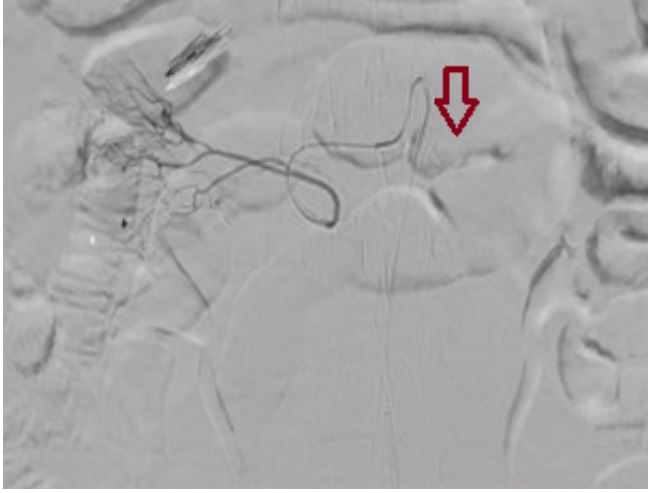

Por persistencia del descenso en la Hb y requerimiento de múltiples transfusiones, se solicitó valoración y manejo por parte del servicio de radiología intervencionista, para embolización. Allí cateterizaron selectivamente el tronco celiaco y, posteriormente, la arteria gastroduodenal, y se embolizó con micropartículas de 300/500 micras. Así, se observó una disminución del aporte arterial al sitio anatómico de donde se localizó la úlcera, pero sin excluir completamente el flujo a la zona, con lo cual la paciente presentó estabilidad de la Hb por más 72 h sin nuevos episodios de melenas y se consideró adecuado el control del sangrado y se le dio egreso al paciente (figura 2).